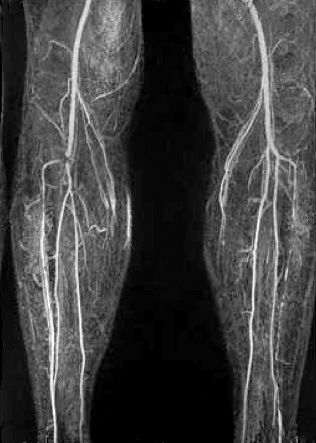

МРТ–ангиография.

Этот метод дает возможность получения трехмерного изображения сосудов без лучевой нагрузки. В применении к варикозному расширению вен этот метод используется для изучения глубокой венозной системы нижних конечностей и малого таза, при подозрении на наличие сосудистых мальформаций, сосудистых опухолей.